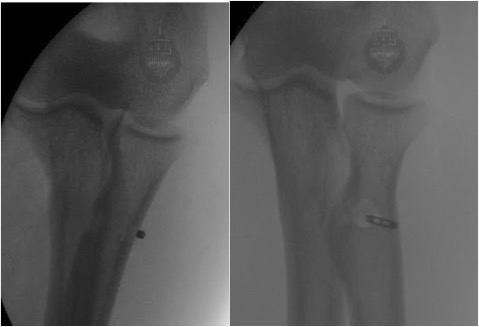

These images show Intra-operative x-rays of the deployed biceps button with the tendon docked in the radial tuberosity